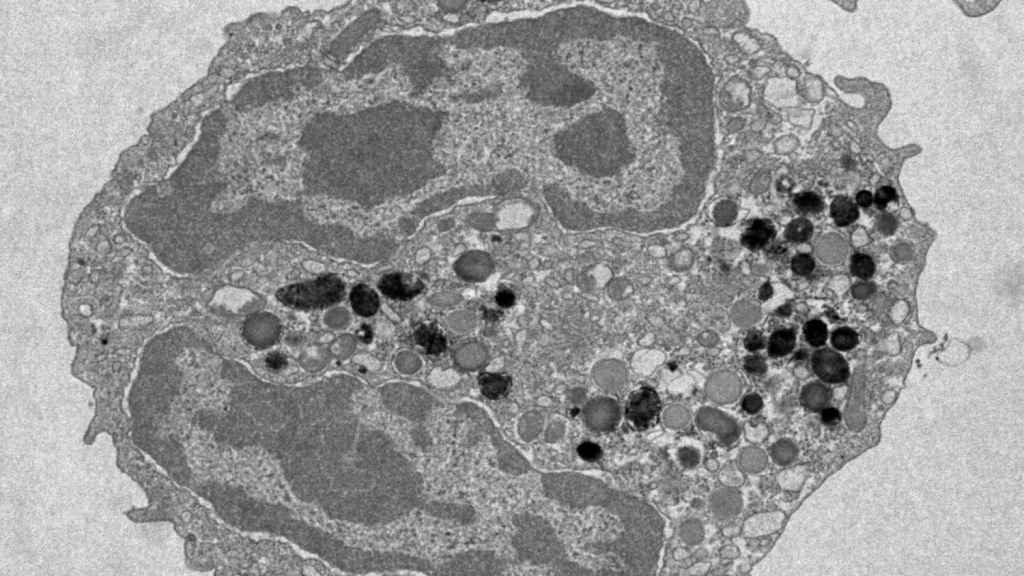

Analyzing blood from over 200 men in each category, the scientists zoomed in on hematopoietic stem cells (HSCs), aka blood stem cells. These cells naturally mutate as we age, which leads to clones with subtly different genetic makeup, a process known as clonal hematopoiesis. While this is normal, certain mutations can cause blood cancers.

Giving blood didn’t affect the cells’ likelihood of undergoing clonal hematopoiesis — it was found to be just as common in frequent donors versus sporadic. However, the researchers noticed that the genetic makeup of blood cells in each group varied when it came to a gene called DNMT3A, which is known to mutate in people who develop leukemia.

This finding spurred the team — who collaborated with scientists in Heidelberg, Germany, with the help of the German Red Cross Blood Donation Center — to conduct follow-up experiments. They decided to edit human HSCs using CRISPR, and then implant the edited cells in mice. The result? When the mice that had blood removed were then exposed to stress imitating that of frequent blood loss, the cells with DNMT3A mutations produced red blood cells to recoup blood supply, and those new cells didn’t turn cancerous.